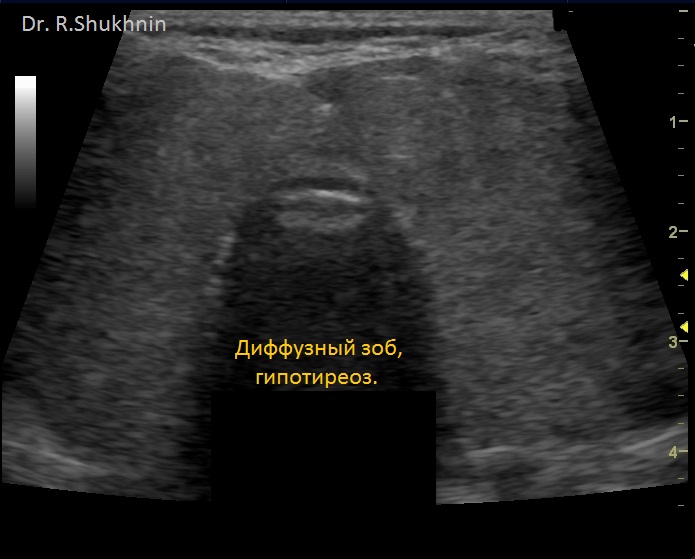

На фото из практики д-ра Шухнина Р.Е.

4) УЗИ щитовидной железы. Диффузный зоб, гипотиреоз. Снижение функции щитовидной железы (гипотиреоз) – причина распространенных отеков, в т.ч. и вокруг глаз.